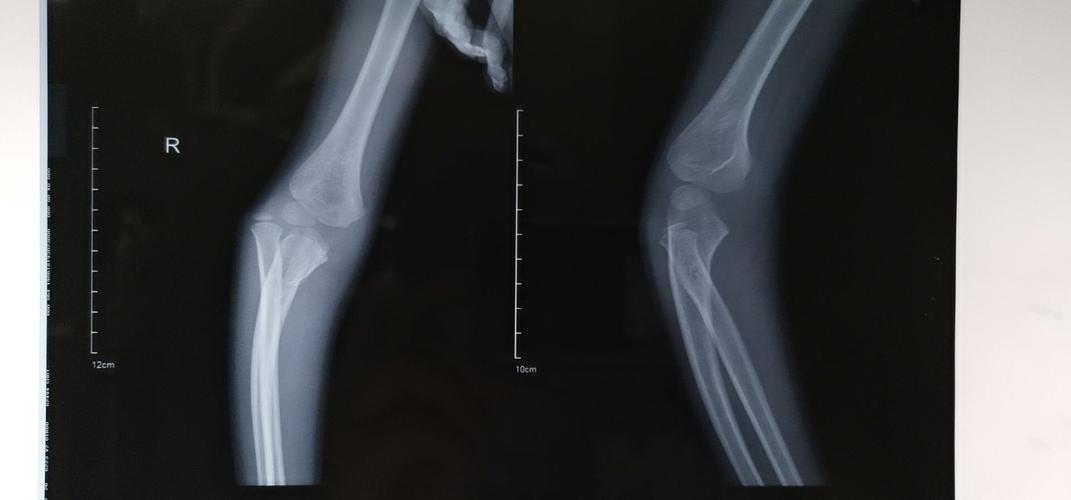

桡骨小头半脱位x线

桡骨小头半脱位x线,小儿桡骨头半脱位图片

右桡骨小头脱位

尺骨鹰嘴骨折伴桡骨小头脱位

桡骨小头脱位x线诊断

桡骨头半脱位x线图片

肘关节脱位x线

桡骨小头脱位x线表现

肘关节脱位x线表现